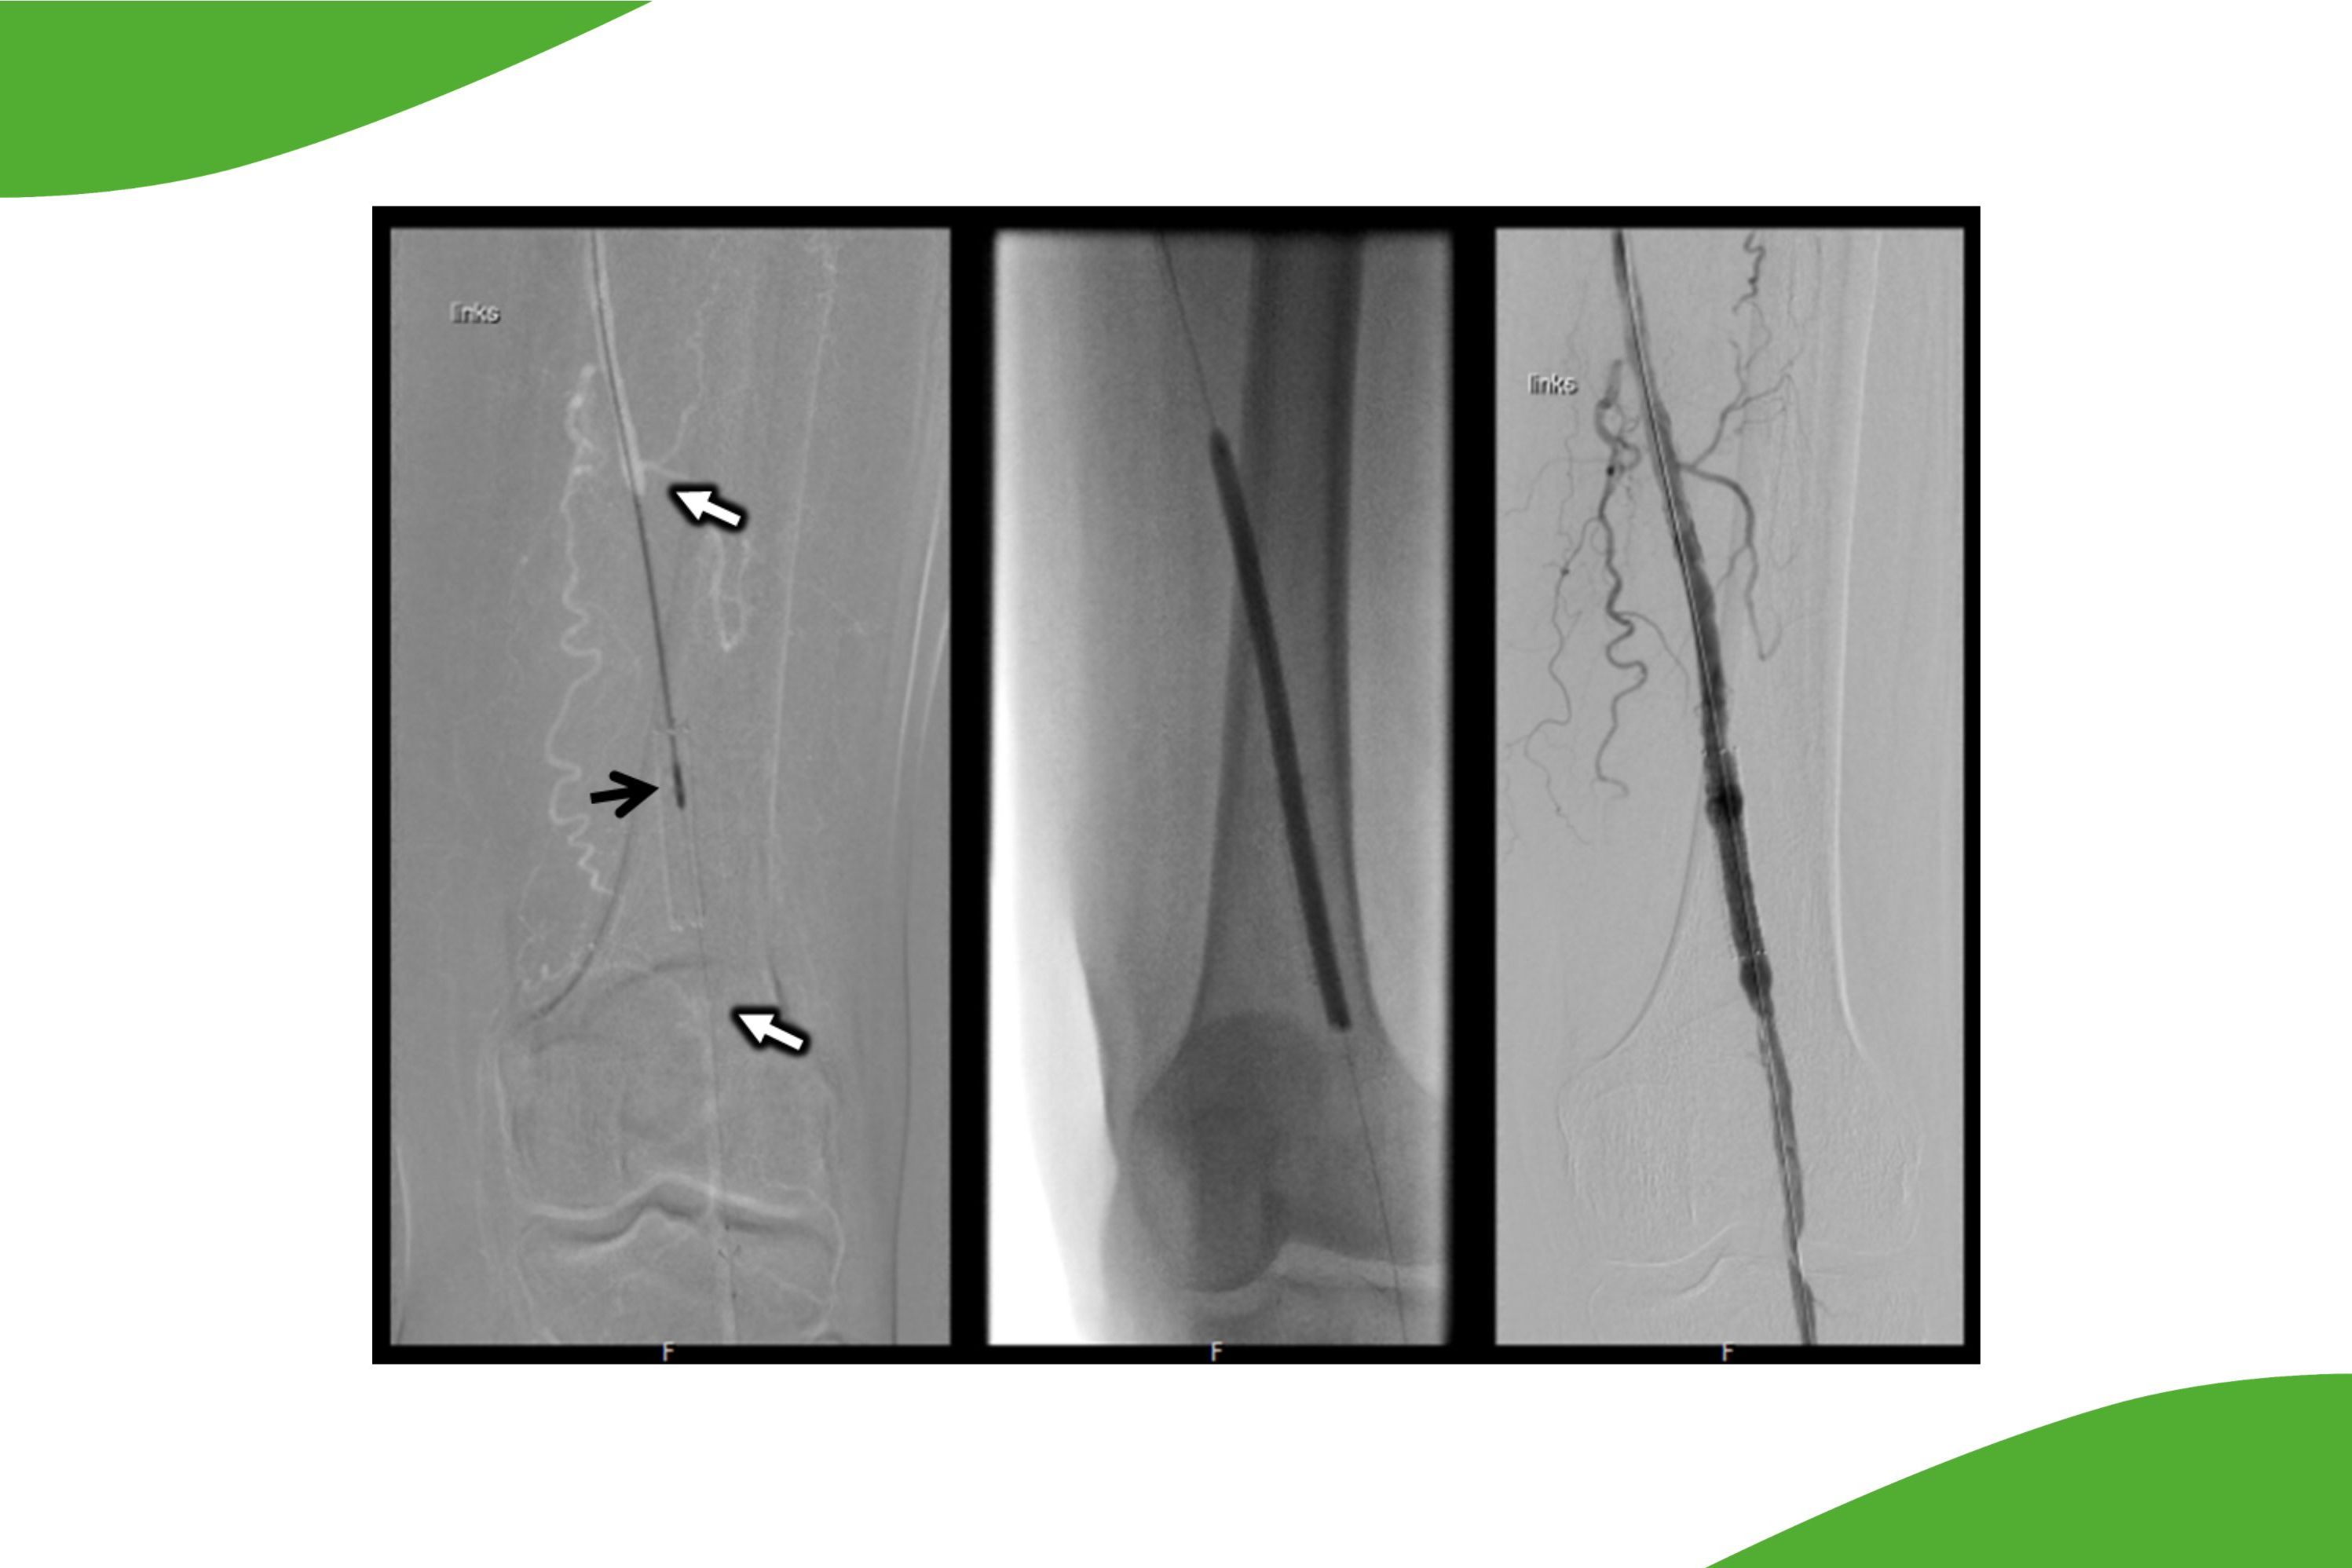

Die Weiterentwicklung von modernen Katheterverfahren ermöglicht es heute nicht nur eine Ballondilatation oder eine Stentimplantation bei Gefäßverengungen oder Verschlüssen durchzuführen, sondern vielmehr auch die Einengungen und Plaques, welche das Gefäßlumen einengen oder verschließen mittels rotierender Messersysteme auszuschneiden und somit das Gefäß wieder zu eröffnen. Diese sogenannten Atherektomien wurden bereits vor vielen Jahren entwickelt, konnten aber aufgrund der Materialbeschaffenheit der Systeme nicht eine weite Verbreitung finden. Die neuen Systeme hingegen erlauben hier mit äußerst niedriger Komplikationsrate und sehr gutem Langzeitergebnis solche Veränderungen komplett aus dem betroffenen Gefäß zu entfernen. Ein typisches Einsatzgebiet für diese Atherektomien sind z. B. Veränderungen auf Höhe der Arterien des Kniegelenkes, da dort konventionelle Stentsysteme durch das Bewegungsausmaß des Gelenkes geschädigt werden können.

Grafische Dartstellung: Distaler Verschluss der Oberschenkelarterie bis ins Bewegungssegment reichend (weiße Pfeile). Nach der durchgeführten Artherektomie und der anschließenden Behandlung mit einem medikamentenbeschichteten Ballon zur perkutanen transluminalen Angioplastie ist die Durchblutung wiederhergestellt.

Grafische Dartstellung einer Artherektomie, der Eingriff wird im Text beschrieben.